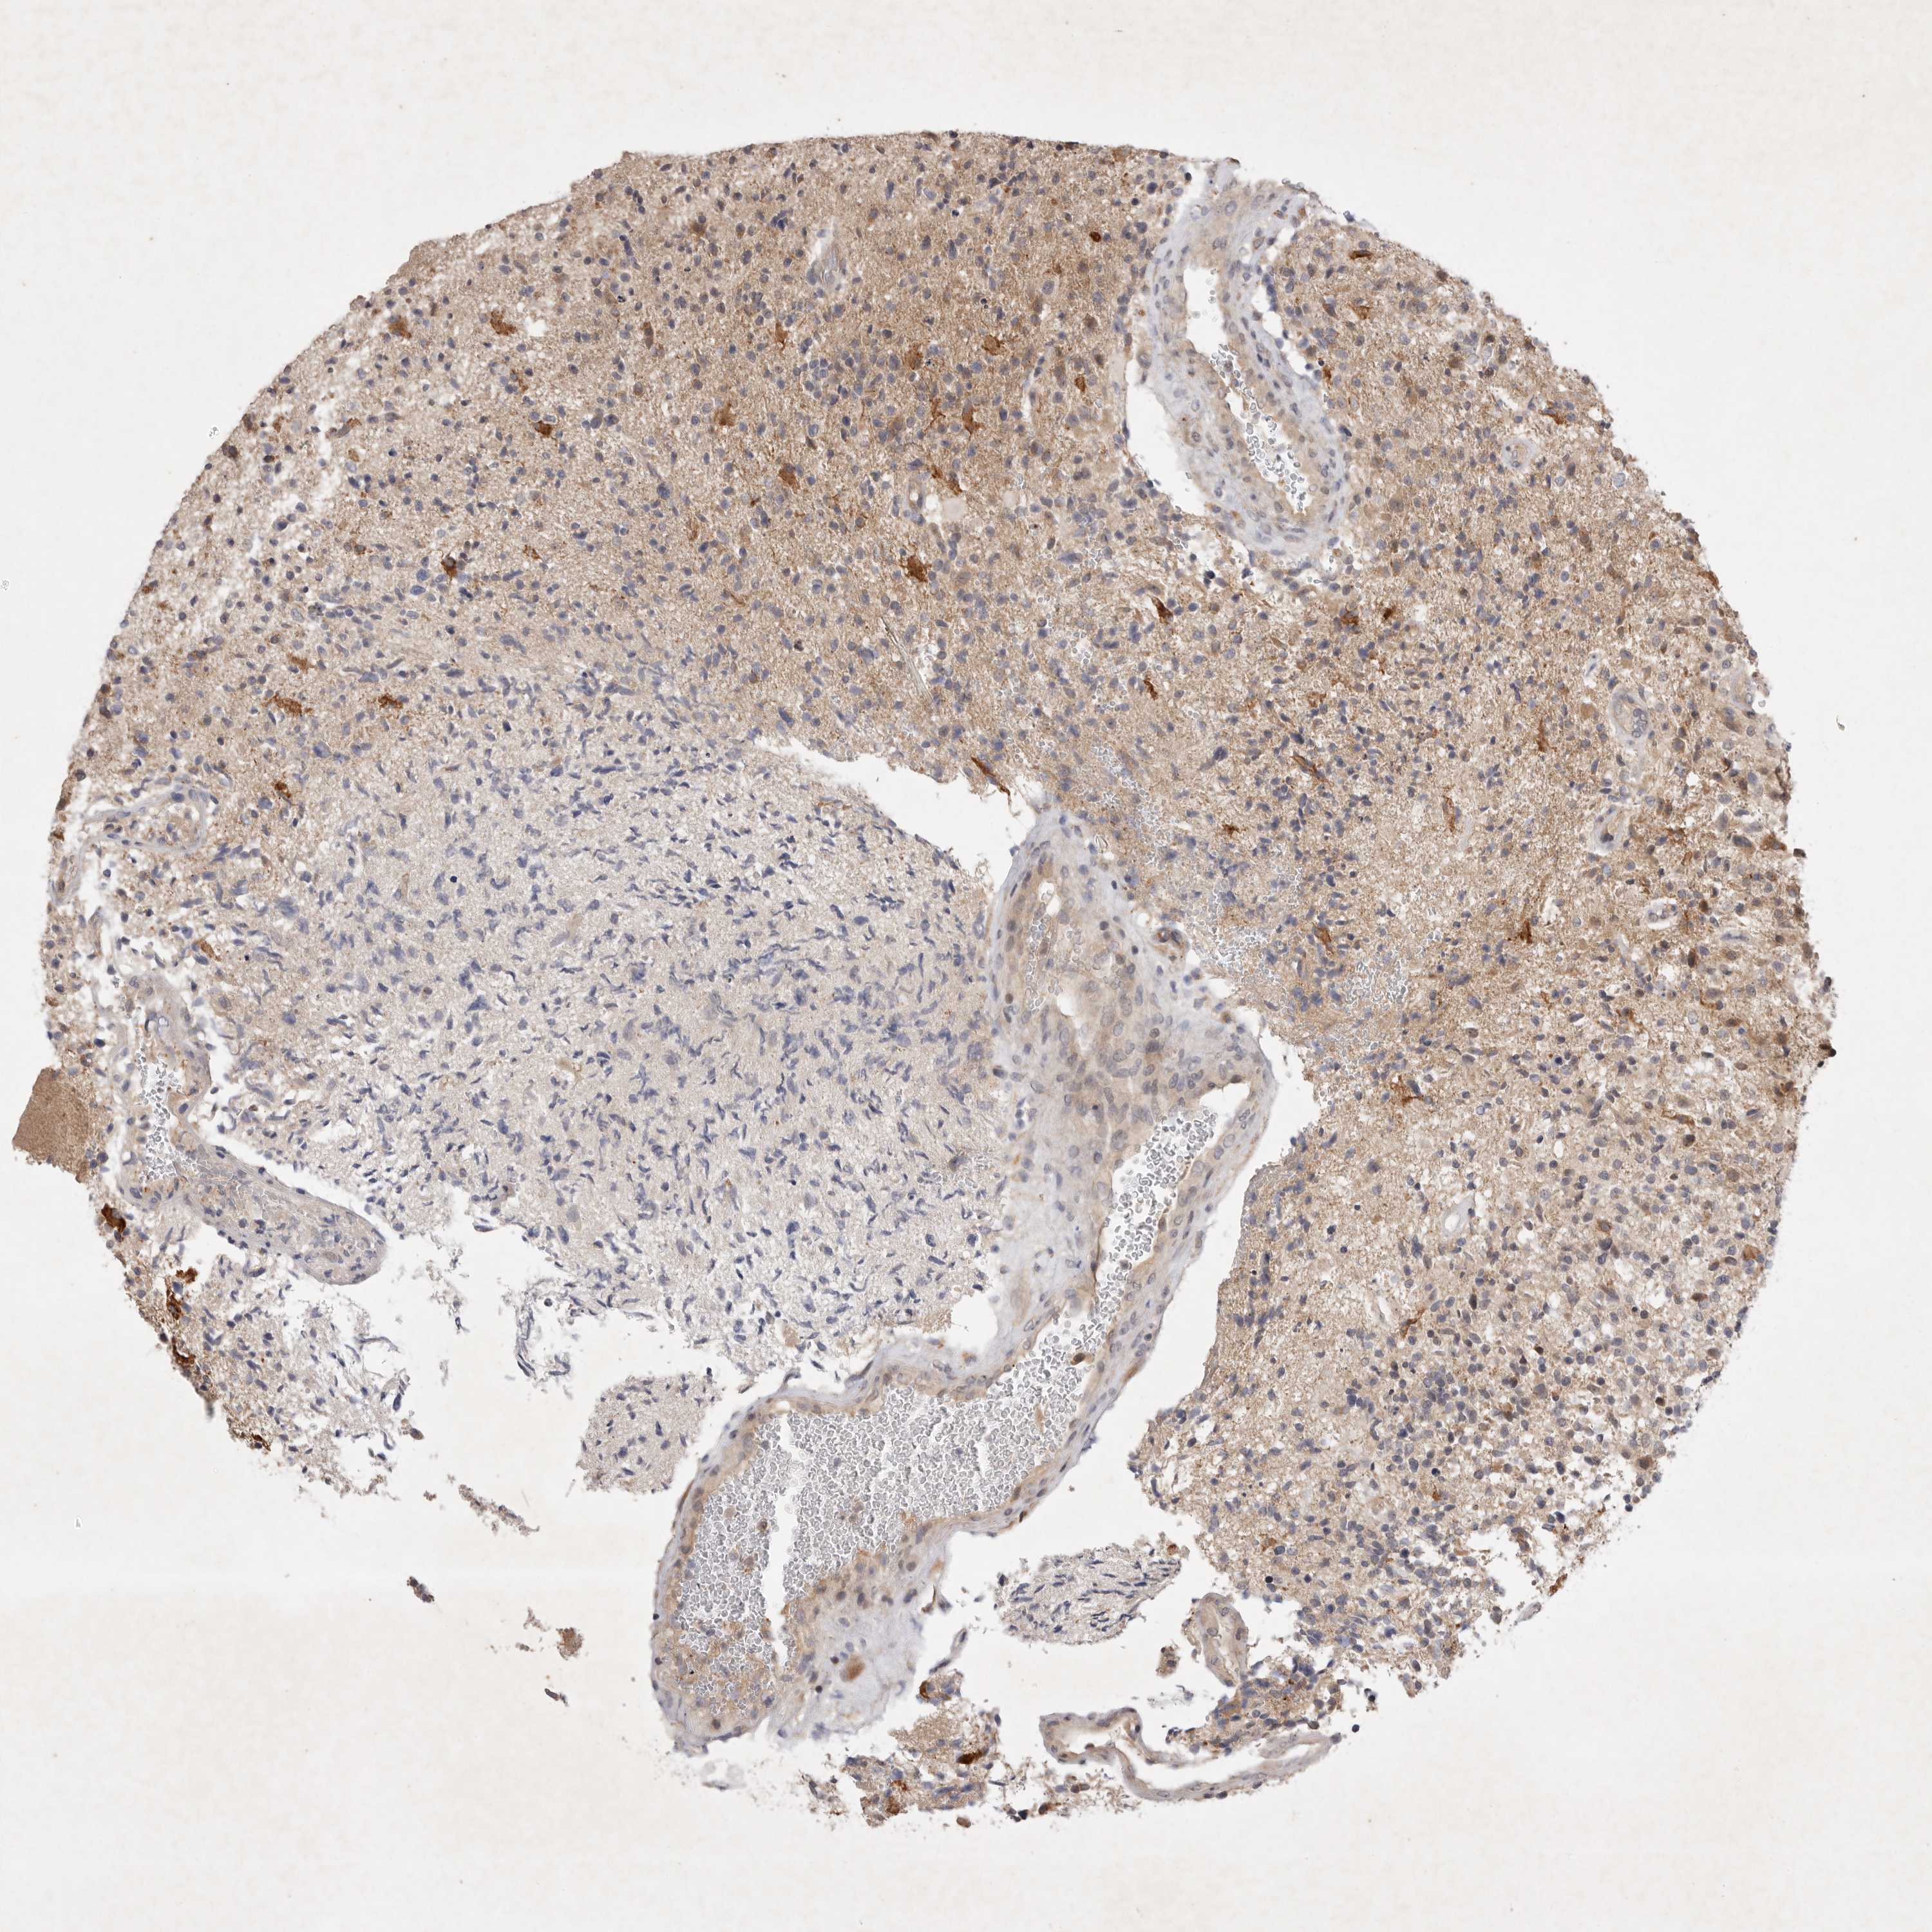

GLIOMA - Protein expressioni

A mouse-over function shows sample information and annotation data. Click on an image to view it in a full screen mode. Samples can be filtered based on level of antibody staining by selecting one or several of the following categories: high, medium, low and not detected. The assay and annotation is described here.

Note that samples used for immunohistochemistry by the Human Protein Atlas do not correspond to samples in the TCGA dataset.

Antibody stainingi

Antibody staining in the annotated cell types in the current human tissue is reported as not detected, low, medium, or high, based on conventional immunohistochemistry profiling in selected tissues. This score is based on the combination of the staining intensity and fraction of stained cells.

Each image is clickable and will lead to virtual microscopy that enables deeper exploration of all samples and also displays staining intensity scores, fraction scores and subcellular localization as well as patient and tissue information for each sample.

Antibody HPA016747

Antibody HPA026832

Staining

High

Medium

Low

Not detected

Intensity

Strong

Moderate

Weak

Negative

Quantity

>75%

75%-25%

<25%

None

Location

Nuclear

Cytoplasmic/membranous

Cytoplasmic/membranous,nuclear

Glioma, malignant, High grade

Glioblastoma, NOS